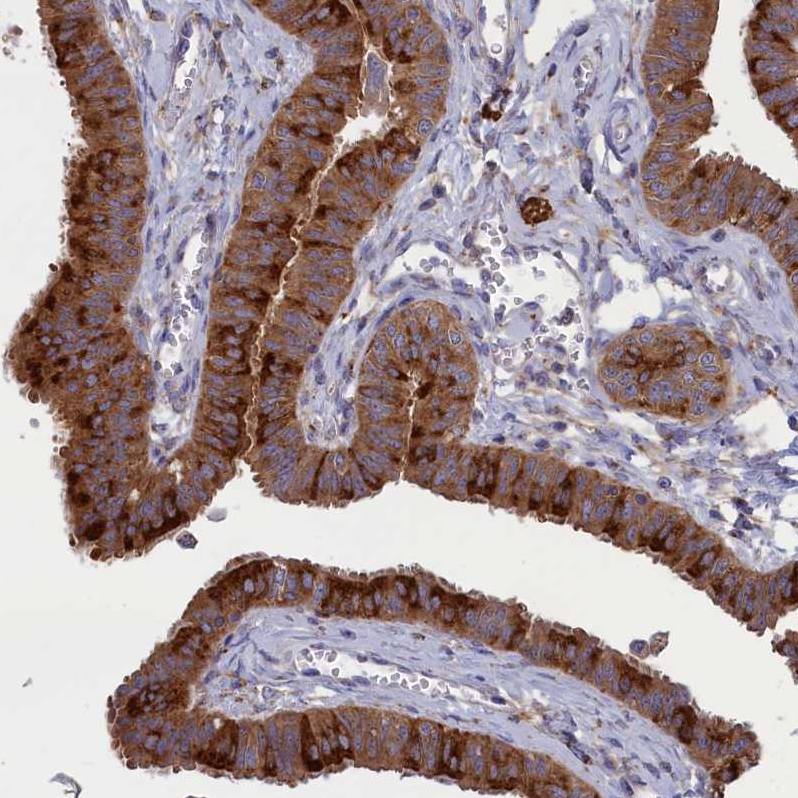

Immunohistochemical staining of human fallopian tube shows strong cytoplasmic positivity in glandular cells.